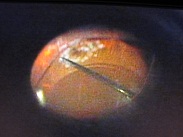

写真だと水色の部分が視神経乳頭(マ盲点)になります。ちなみに、物を見る中心部の網膜は黄斑と呼ばれ、オレンジの矢印に当たります。